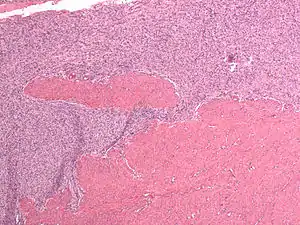

| Micrograph of a low-grade endometrial stromal sarcoma. H&E stain. | |

Low-grade endometrial stromal sarcoma consists of cells resembling normal proliferative phase endometrium, but with infiltration or vascular invasion. These behave less[3] aggressively, sometimes metastasizing, with cancer stage the best predictor of survival. The cells express estrogen/progesterone-receptors.

Microscopy

- Monotonous ovoid cells to spindly cells with minimal cytoplasm.

- Prominent arterioles. Angiolymphatic invasion common.

- Up to 10-15 mitotic figures per 10 HPF in most active areas.

- Tongue-like infiltration between muscle bundles of myometrium.

- May exhibit myxoid, epithelioid and fibrous change.

- May have foam cells or hyalinization in the stroma.